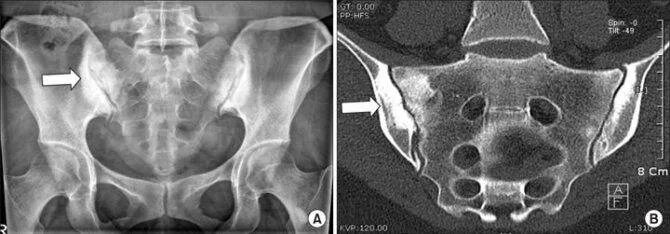

Мрт пояснично крестцового отдела тазобедренные суставы